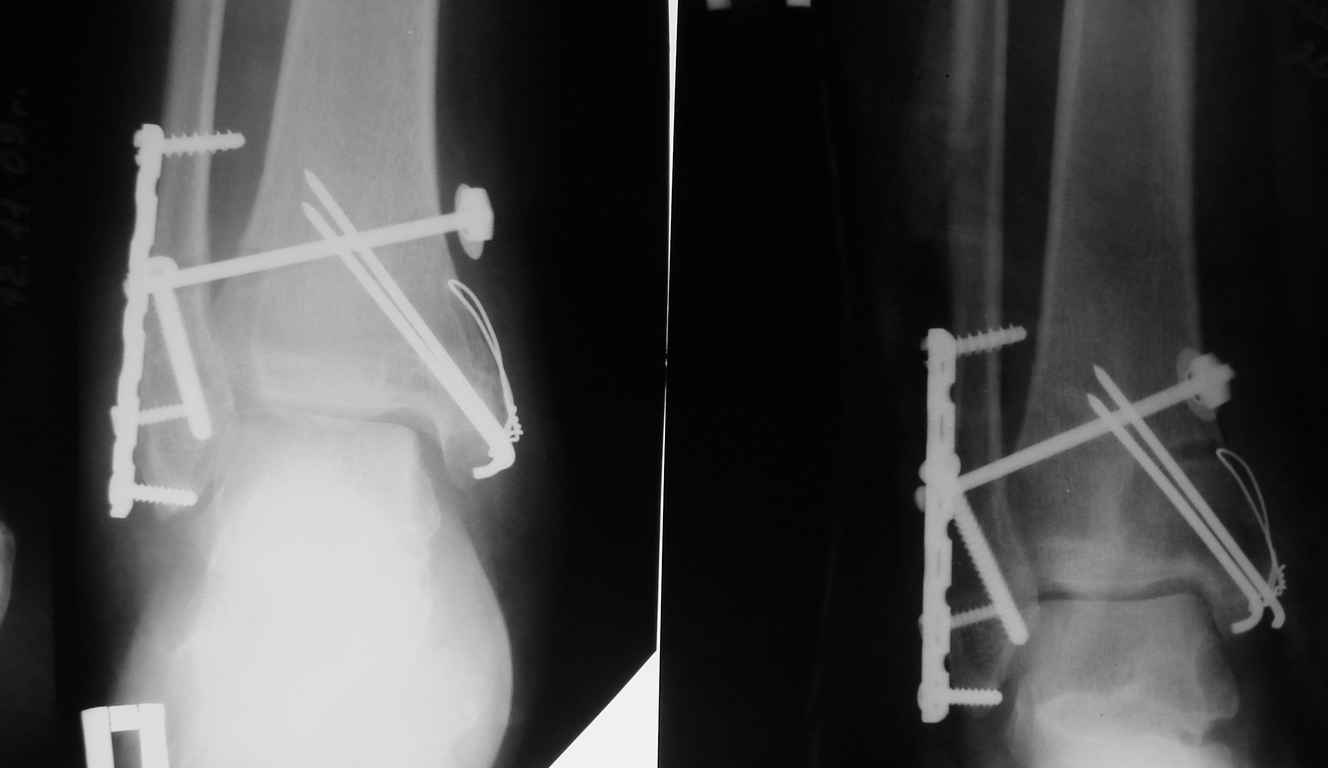

Здесь несколько частных случаев: перелом голеностопа со сравнительными снимками и разрыв синдесмоза, а также медиальная Hook пластина.

Нет первичных снимков, перелом очень низкий и под большим сомнением диагноз разрыва синдесмоза. Медиальная сторона отрепонирована на "хорошо" и, по-видимому, прорезание проволоки произошло во время операции. Без снимков трудно судить о высоте малоберцовой, а лодыжка находится в варусе. Лагирование получилось, но возле тонких шурупов передне-задний шуруп выглядит немного тяжеловато.

Во всех руководствах АО имеется описание техники применения низкопрофильных пластин 1/3 трубки, которые могут быть применены для фиксации наружной лодыжки. Фиксацию проводят кортикальными 3.5 мм шурупами, и если дистальная фиксация недостаточная, тогда усиливают конструкцию созданием hook plate. Сгибая конец пластины на последнем отверстии, внедряют его в дистальный отдел, и тем самым создается дополнительная фиксация.

Современные преконтурированные пластины не имеют таких недостатков, и разделяются на правые и левые, а также на латеральные и задние. Множественные дистальные шурупы 2.7 мм уменьшают подкожное раздражение, и такой имплант можно оставить на долгий срок без удаления.

Для молодых достаточным бывает обычная лодыжечная пластина без блокировки, и только у пожилых с остеопорозом лучше взять полиаксиальные пластины с угловой стабильностью.

Медиальная лодыжка фиксируется каннюлированными лодыжечными шурупами перкутанно, а неточная репозиция (интерпозиция) является показанием к открытой технике. При больших вертикальных фрагментах нужны противоскользящие медиальные пластины.